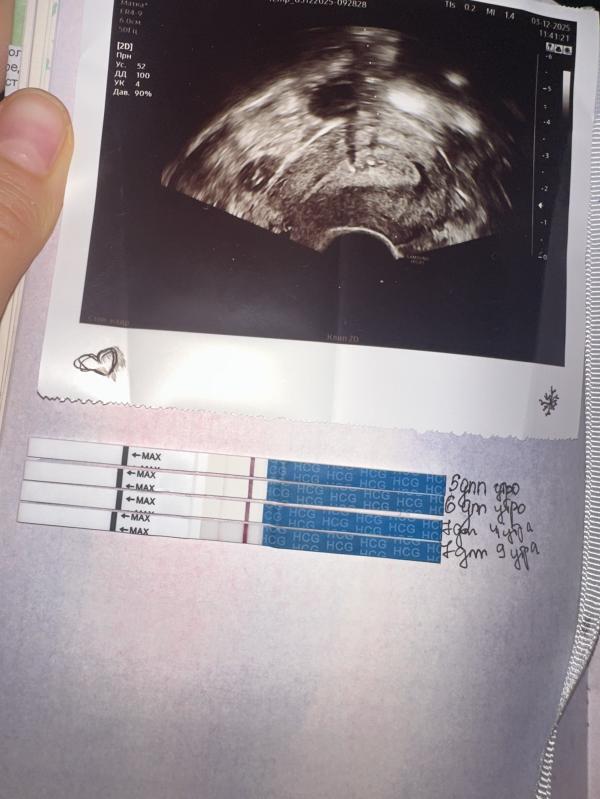

я тоже вижу вторую полоску. Надеюсь у вас все получится. Хгч не сдавали ?

Ярче точно стал. Нужно полежать, успокоиться. Поддержка хорошая. Сдавайте хгч в динамике

7дпп, со вчера вечера началась коричневая мазня, тянет живот как перед месячными, по инструкции от врача добавила масло прогестерон , транексам и 3 укола этамзилата с промежутками в 5 часов , выпила ношпу, ночью было плохо прям( утром выделения были уже с прожилками , все еще рисует вторую полоску , но кажется ярче не становится🥲Сказать , что я в панике, ни чего не сказать, поддержите хорошими историями 😭😭😭